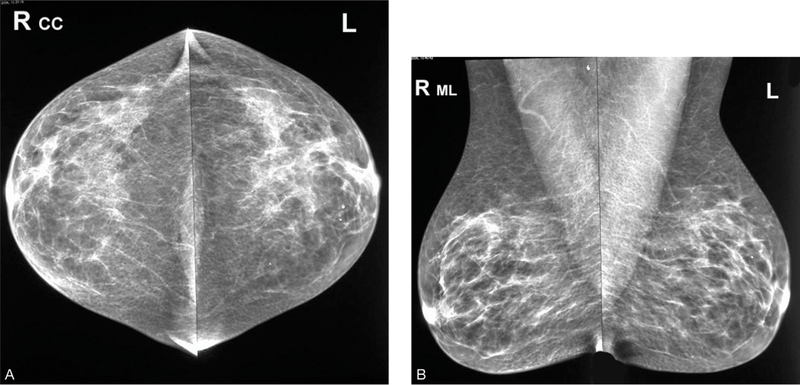

BIRADS trên nhũ ảnh là là sự phân loại dựa trên một hệ thống tiêu chuẩn để mô tả các phát hiện và kết quả chụp nhũ ảnh (được gọi là Hệ thống dữ liệu và báo cáo hình ảnh vú hoặc BIRADS - Breast Imaging Reporting And Data System) của Hiệp hội Điện quang Hoa Kỳ (ACR - American College of Radiology) sắp xếp các kết quả thành các phân mục được đánh số từ 0 đến 6.

Sang thương có thể lành tính, cần được theo dõi trong thời gian ngắn.

Sang thương có khả năng trở thành ung thư là rất thấp (không quá 2%). Nhưng vì nó không được chứng minh là hoàn toàn lành tính, nên cần kiểm tra xem sang thương có thay đổi theo thời gian hay không. Bạn sẽ cần tái khám định kỳ theo dõi hình ảnh lặp lại sau 6 đến 12 tháng và thường xuyên sau đó cho đến khi kết quả được ghi nhận là ổn định (thời gian ít nhất là 2 năm). Cách này giúp tránh sinh thiết không cần thiết, đồng thời nếu sang thương thay đổi theo thời gian, nó cũng cho phép chẩn đoán sớm.